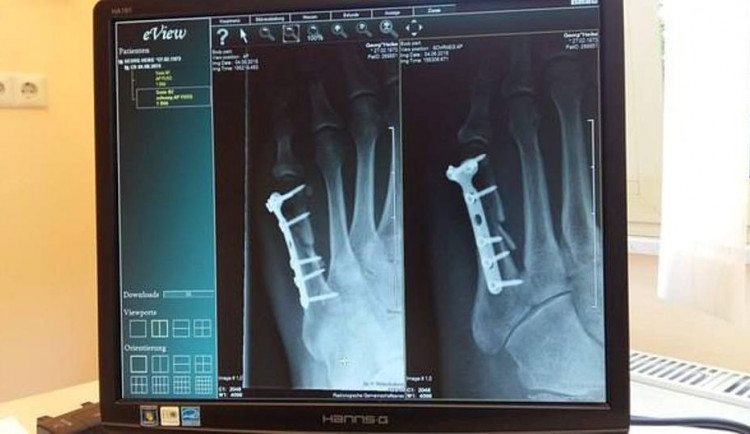

Přes šest milionů korun stálo nemocnici v Novém Městě na Moravě zakoupení a instalace nového rentgenu. Má kvalitnější zobrazení a zároveň pacienty vystavuje nižší radiační zátěži, uvedla mluvčí nemocnice Tamara Pecková. Přistroj nemocnice zaplatila z dotací, nutnou úpravu prostor včetně nové nosné konstrukce pro přístroj hradila z vlastního.

Nový rentgen stál 5,7 milionu korun, náklady na úpravu místnosti včetně výměny oken, dveří, instalace žaluzií, antistatických podlah a opravy vzduchotechniky vyčíslila nemocnice na 500 tisíc korun.